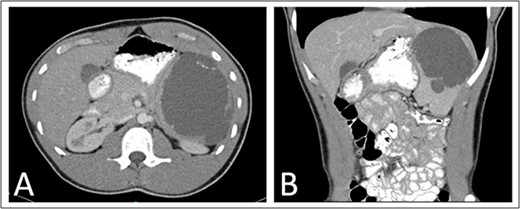

As part of his workup, he underwent an abdominal ultrasound showing a 12 cm cystic or hemorrhagic lesion, likely splenic in origin, with an adjacent 5.6 cm complex septated lesion within the spleen. Subsequent abdominal CT showed a 12 cm in greatest diameter complex cystic lesion within the spleen with peripheral and septal calcification with no solid enhancing component (Fig. 1). His blood work, including complete blood count, complete metabolic panel, and coagulation markers, were all within normal limits.

Preoperative (A) axial and (B) coronal abdominal CT images showing complex cystic splenic mass.